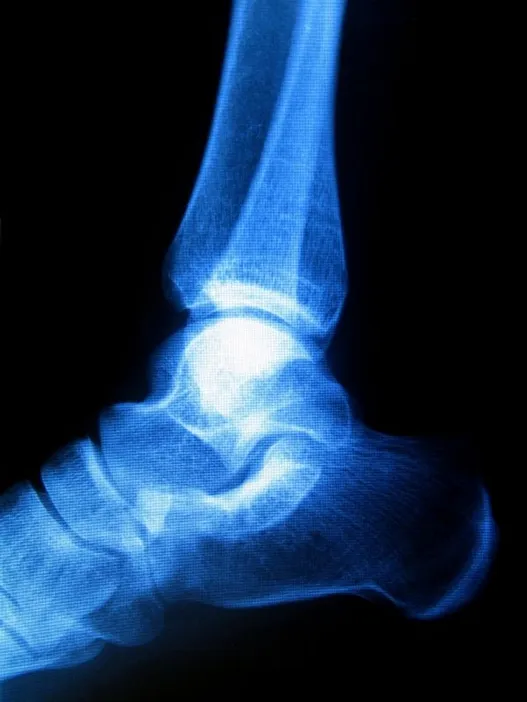

Haglund's Deformity

haglunds deformity

Sometimes known as “pump bump” because of its prevalence among women who wear pump-style shoes, Haglund's deformity can occur in one or both of the feet. If you are suffering from Haglund's deformity, you will most likely have noticed a bony enlargement at the back of the heel. This inflammation is caused when the bursa, a fluid­-filled sac between the Achilles tendon and your heel bone, becomes irritated. Other signs of Haglund's deformity include pain where the Achilles tendon and the heel meet, swelling, and redness.

While genetic factors influence your likelihood to develop Haglund’s deformity (high arches, a tight Achilles tendon), stiff shoes are also a major risk factor.